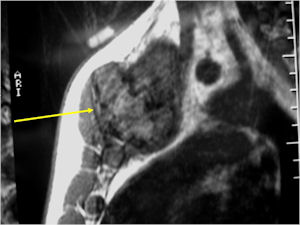

CT Scan:

- More useful for detecting mineralization and evaluating extent of bone destruction than plain X-ray

MRI:

- Also useful in determining extent

- There is often extensive edema around the tumor in the surrounding bone and soft tissues that can lead to a misdiagnosis of a malignant tumor.